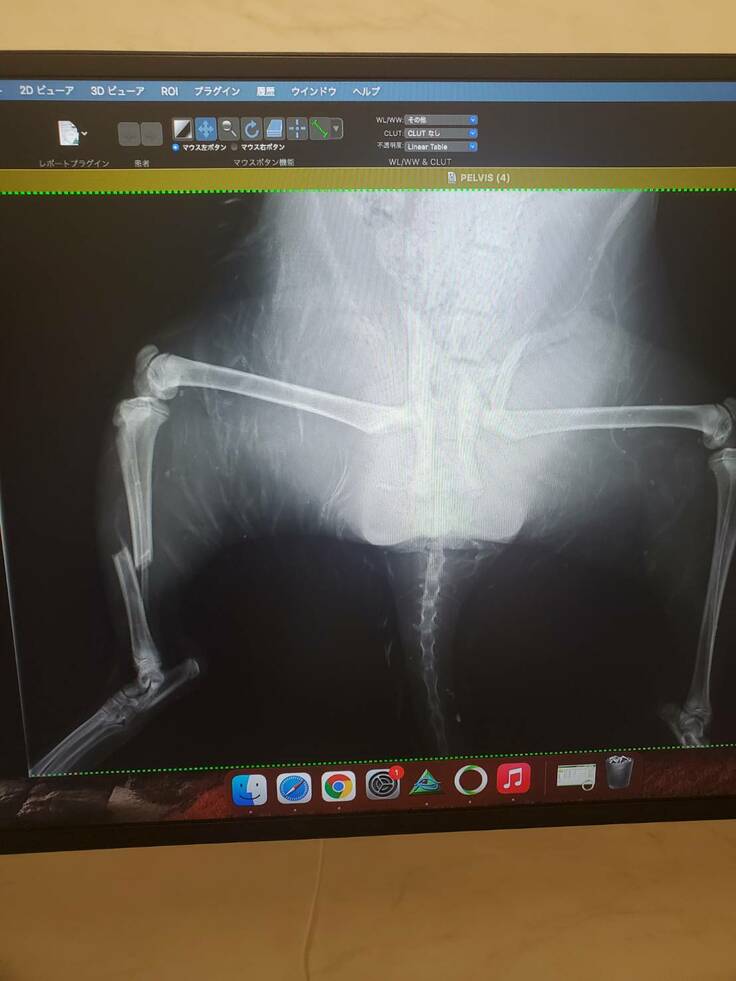

会社の近くを歩いていると猫の鳴き声が聞こえてきました。

4メートルほどの高さのある川を見ると

ずぶ濡れの毎日見かける地域猫がいました。

すぐにハシゴをかけて救出することに。

すると足がぷらぷらで…

自分が仕事中だったため仕事が休みだった彼女に来てもらいすぐに病院に連れて行ってもらうことに。

恐らく車に跳ねられて川に落ちたのだろうと。

結果は両脚の骨折と骨盤の骨折という診断に。

しかし骨盤骨折の手術はかなりの高額との事。